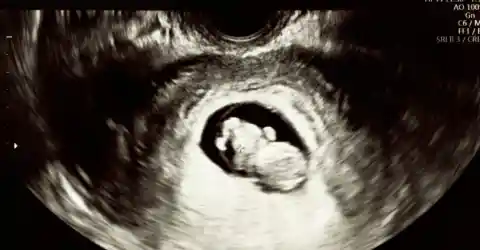

The pathologist sat across from Sarah and Mark, eyes steady. “Your tissue contains fetal DNA,” she said softly. “We identified genetic markers that don’t match your own. In other words, you have retained fetal tissue.”

The doctor explained a rare medical phenomenon—when a pregnancy implants outside the uterus (an abdominal or ectopic pregnancy), the fetus can die and be too large to be reabsorbed. The body sometimes calcifies the remnant to isolate it—a lithopedion, or ‘stone fetus’—allowing it to remain for years. Recent medical literature documents retained calcified fetal remnants lasting decades, with retention times reported from a few years to many decades.

How It Happens

The doctor continued gently: an abdominal ectopic pregnancy can progress undetected if it doesn’t cause immediate catastrophic bleeding. When the fetus dies and cannot be expelled or reabsorbed, the immune system may deposit calcium around it, essentially “walling it off.”

This calcification prevents infection and inflammation, and a remnant can remain asymptomatic for years. Though extremely rare, fewer than a few hundred cases have been reported worldwide; clinicians rely on imaging and pathology, including DNA testing, for diagnosis.